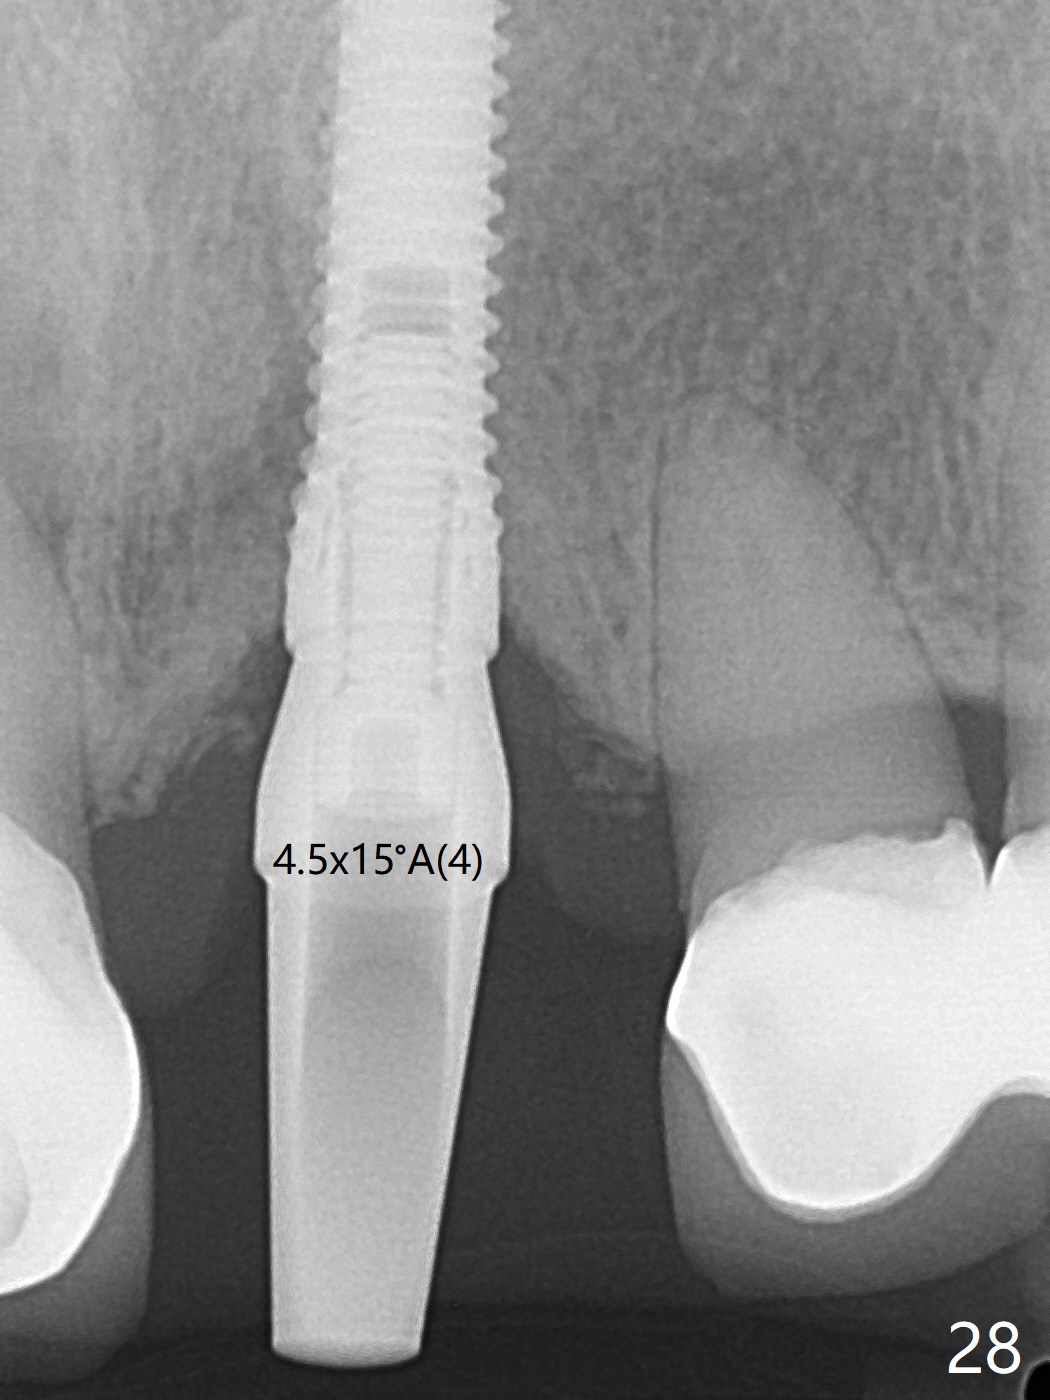

The buccal contour at #9 seems to be slightly concave preop (Fig.1,2 (*)). In fact the buccal plate is found to be lost when the tooth is extracted. Osteotomy is initiated as palatal as possible apical, but the occlusion dictates the coronal end of the osteotomy should be buccal, leaving the buccal gap ~ 2 mm for bone graft. The initial osteotomy (18 mm deep) appears to be close to the Incisive Foramen (Fig.3 blue dashed line). The nasal floor appears to be intact when the drill is removed. Subsequent osteotomy is adjusted so that the apical end of the osteotomy moves distal; when a 3.8x15 mm dummy implant is partially placed, there is clearance (Fig.4). It remains so when a definitive implant is seated (Fig.5); Vanilla graft is placed (Fig.5 *) before placement of a 4.5x5.5(3) mm abutment. More allograft is placed when an immediate provisional is fabricated (Fig.6 arrow and *). The gingiva remains to be recessive 1 month postop (Fig.7). It seems to be related to the bulky gingival margin of the provisional (Fig.8 *). After trimming the latter (Fig.9 *), the gingival margin immediately returns close to normal (Fig.10). The gingival margin is even between #8 and 9 two months postop, but the bone graft is exposed apically (Fig.11 ^). It may heals by itself. Otherwise debridement, regraft, PRF and suture are pending. The coronal portion of the socket heals 4 months postop (Fig.12). The gingival cuff forms by the immediate provisional (which is removed for impression) 4 months postop (Fig.13 *). While the full Zirconia crown at #7 remains intact (Fig.14), the PFM at #9 has porcelain chip (Fig.15). It is partially due to the occlusion; while the crown at #7 has clearance with the opposing dentition (Fig.16 *), the one at #9 has no. The access hole at #9 (Fig.17 *) seems to weaken the crown structure. There is no access hole at #7. No solid posterior support is another contributing factor for chip (Fig.18). The buccal plate has mild atrophy at #7 and 9 (Fig.19 *). A piece of bone graft is being expelled apically at #9 (Fig.20 >) and is removed subsequently (Fig.21). Before impression for repacking porcelain, the opposing incisal edge has been shortened (Fig.22 arrows, as compared to Fig.16). Since the ideal access hole is at the incisal edge (Fig.25 black circle), buccal to the existing one (Fig.24 A), the abutment is torqued before the repaired crown is recemented (Fig.23). Finally the crown has occlusal clearance (Fig.26). Porcelain chips again around the access hole of PFM 1.5 years post 2nd cementation. The dense bone at the crest (*) cannot explain why the abutment is not loose, since it remains incompletely seated (>). As it was trimmed short, an angled abutment is used (Fig.28). The coronal end is lingual, while #9/24 is edge to edge. The lingual aspect of the coronal end of the abutment is heavily trimmed to reduce bulkiness. To prevent chip, Zirconium crown will be fabricated in spite of the fact that it does not match the PFM of #8 (potential shade discrepancy). The patient is pleased with the new Zirconia crown (Fig.29).